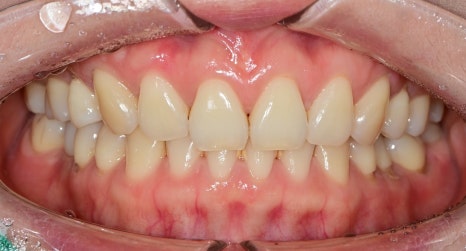

웃을 때 스트레스인 치아

라미네이트로 해결

과거에 발치 교정을 하신 경우

발치된 공간으로 앞니를 밀어 넣다 보니

위에서 찍은 사진을 봤을 때

앞니 쪽이 둥근 아치를 그리지 않고

평편한 곡선을 그리고 있습니다.

이렇기 때문에 앞니가 안쪽으로 말려 들어가 보이고요

정면 사진은 치아의 형태가 너무 각져있어 남성형 같은

치아를 보이고 있습니다.